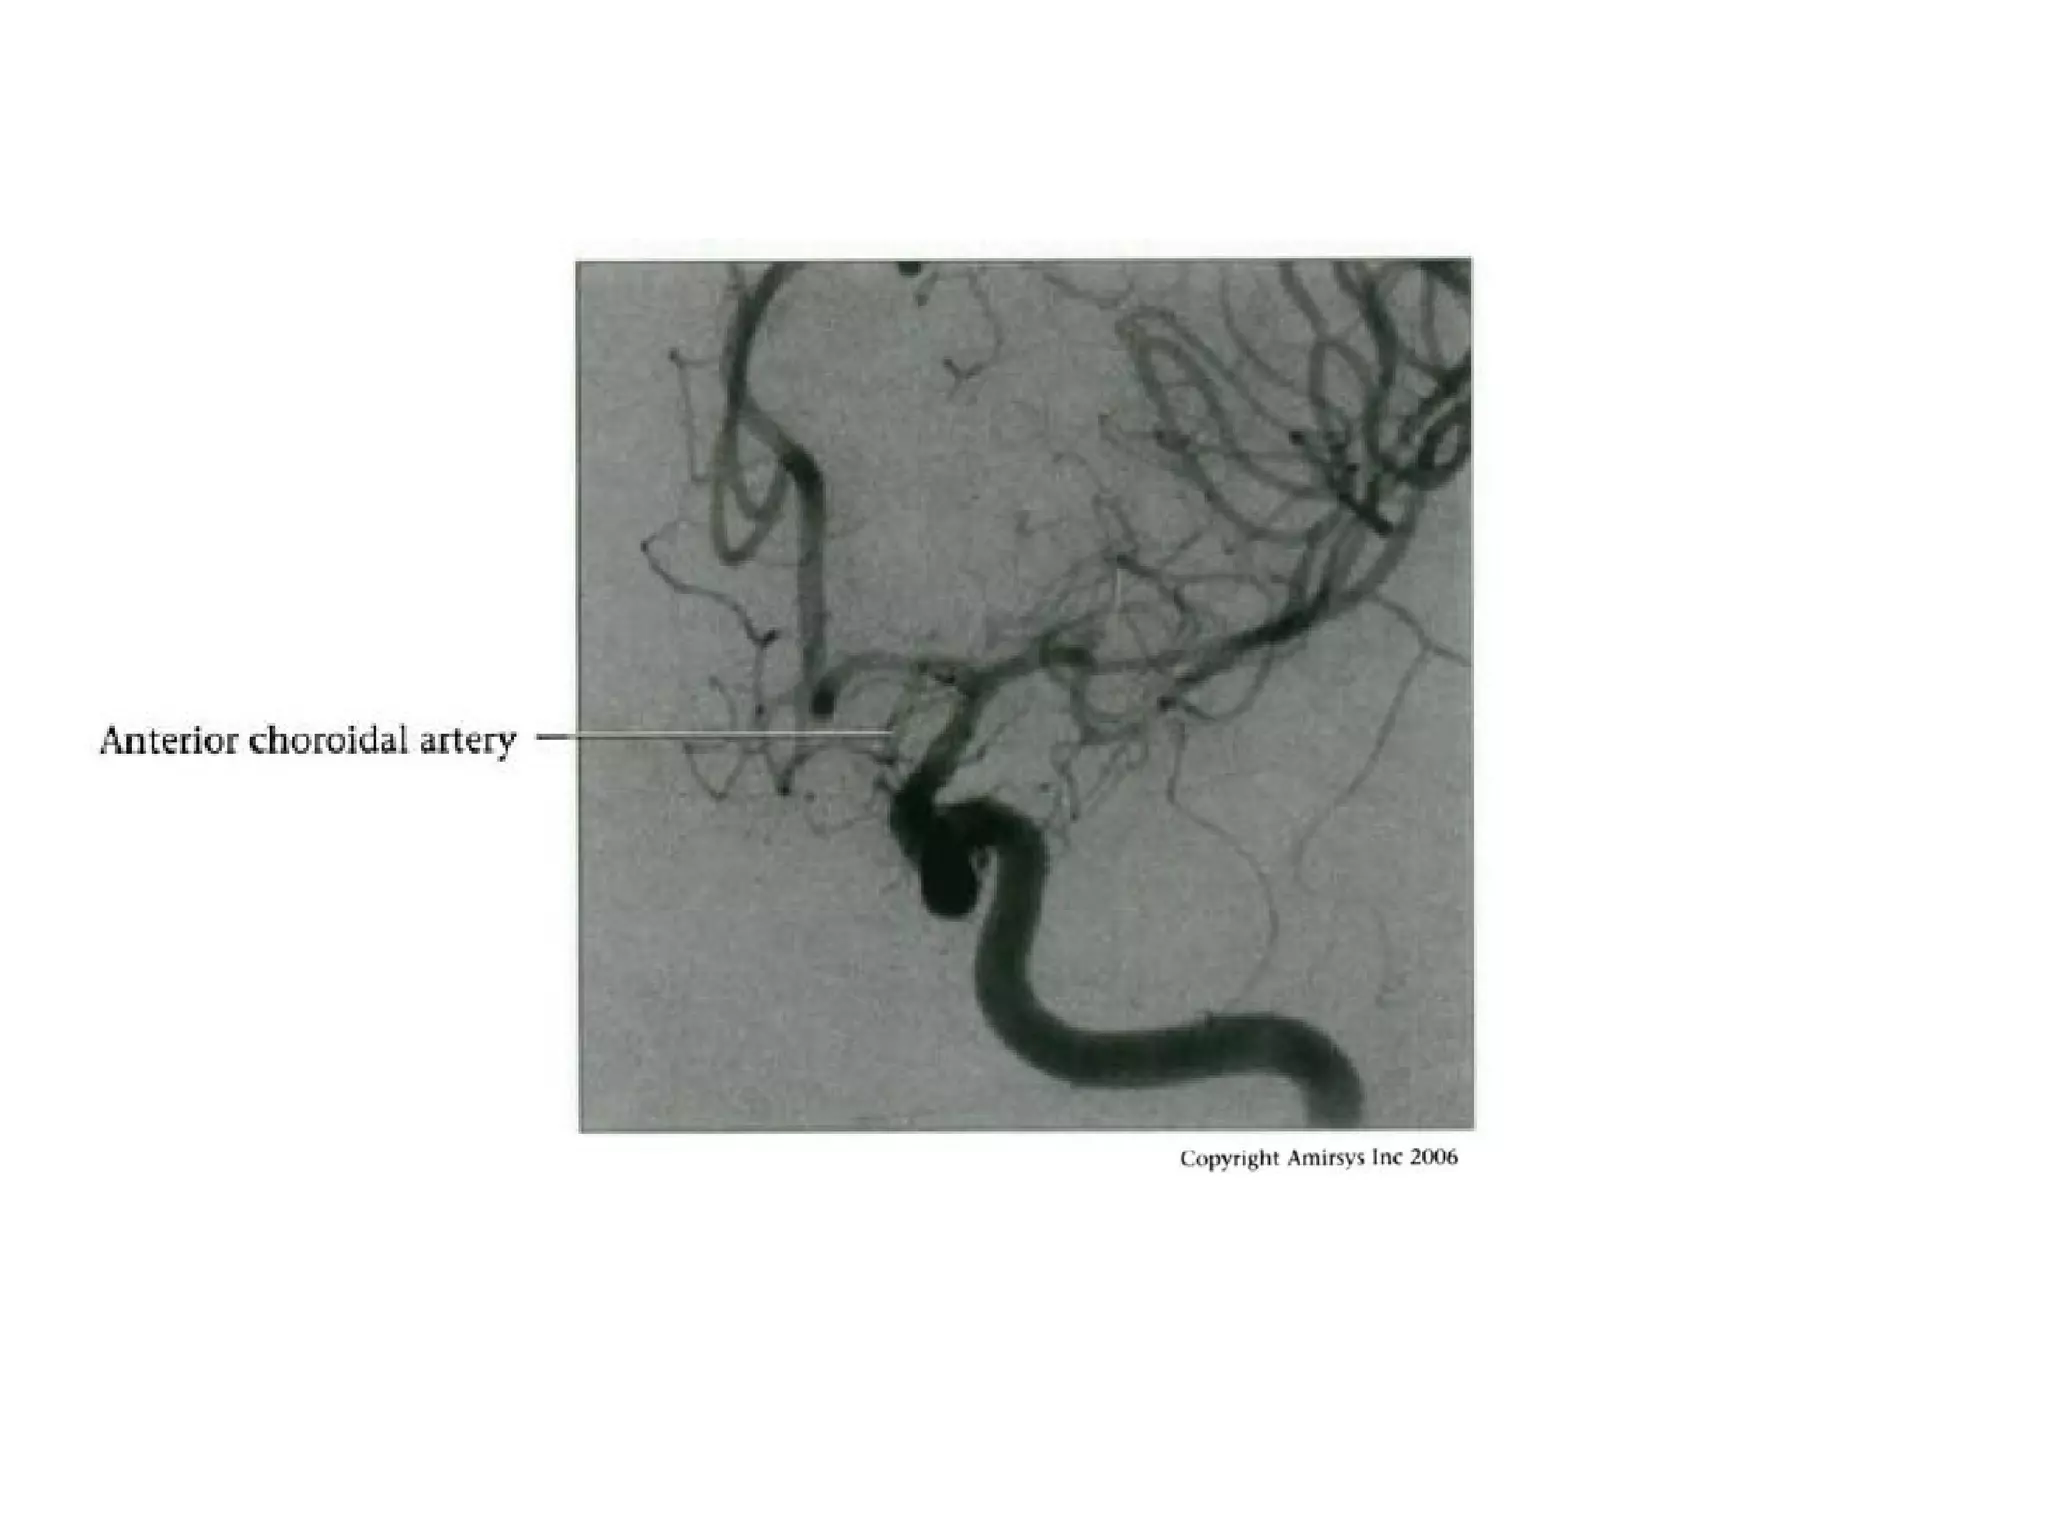

Hyperplastic Anterior

Choroidal Artery

• The anterior choroidal artery, usually a small vessel,

arises from the supraclinoid internal carotid artery just

distal to the posterior communicating artery.

• From there it subdivides into important branches that

supply the cerebral peduncle and optic tract.

• The temporo-occipital branches of the posterior cerebral

artery may arise from the anterior choroidal artery.

• In people with this cerebrovascular variant, the anterior

choroidal artery is described as hyperplastic.

• The prevalence of hyperplastic anterior choroidal arteries

is reported to be 1.1%–2.3%.

RadioGraphics 2009; 29:1027–1043